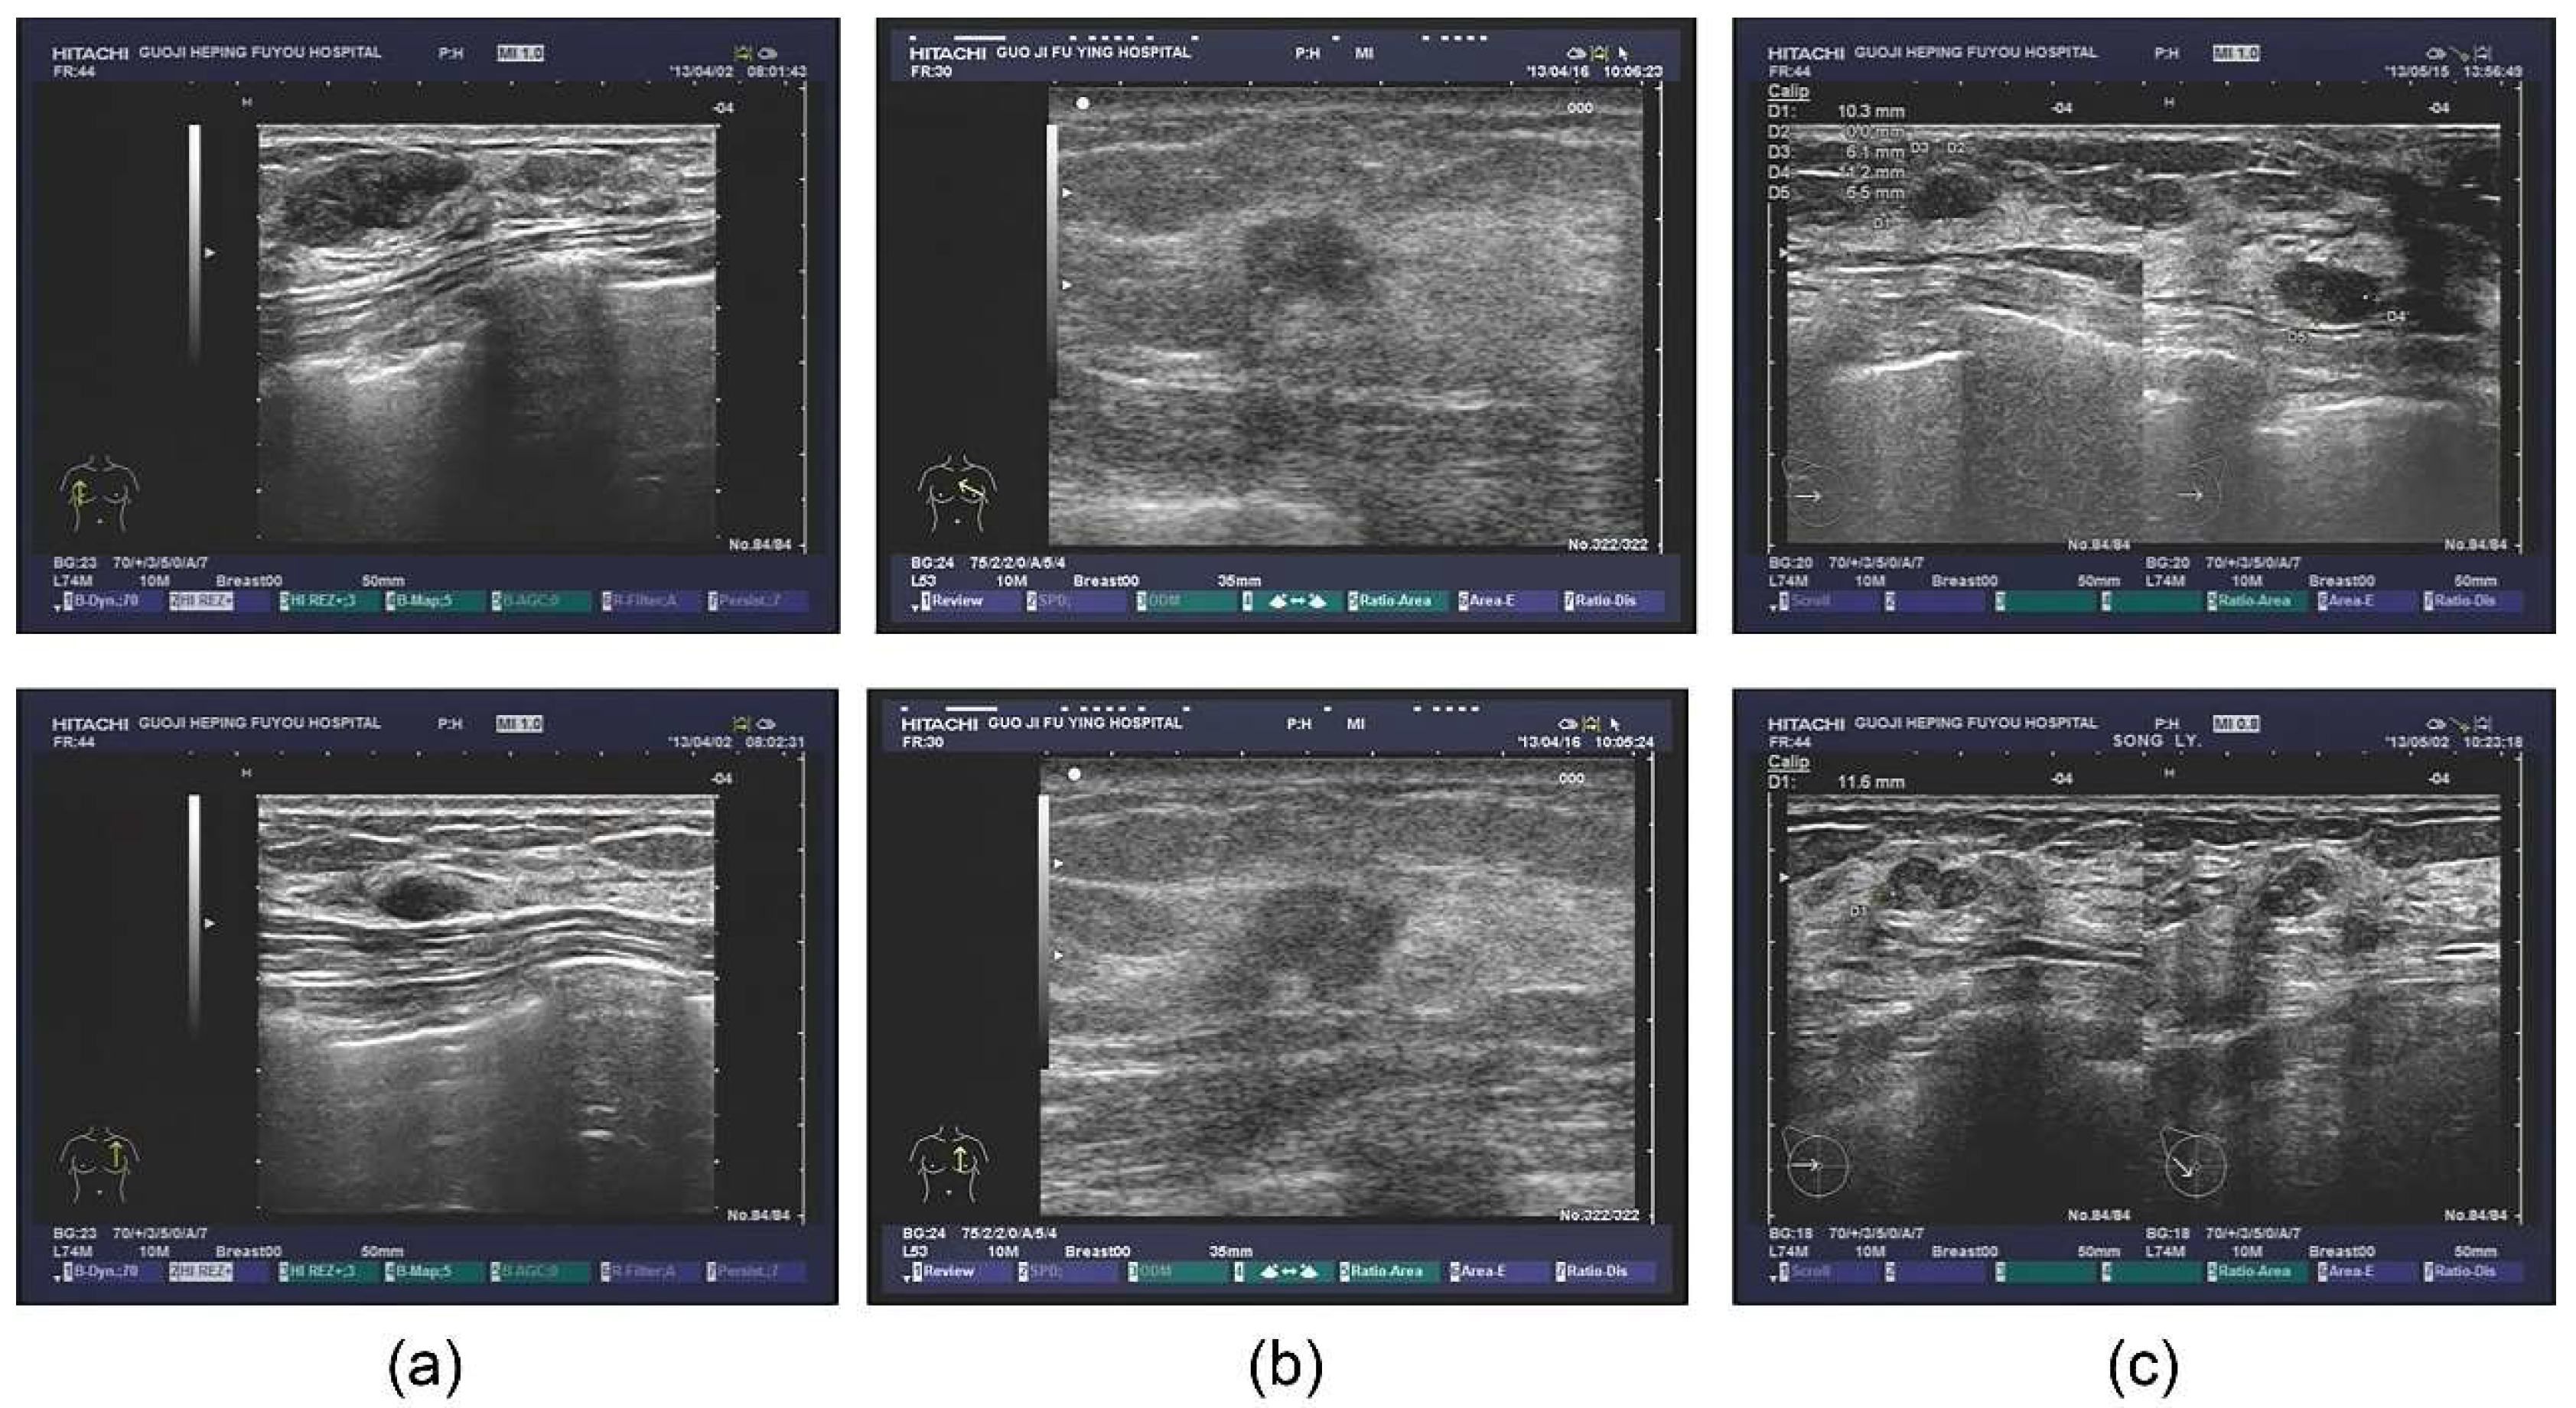

The database also contained extensive information, including outpatients and tips derived from the ultrasonic information, as well as the corresponding pathological diagnosis. Some patients also underwent the molybdenum target examination and a molybdenum target conclusion was obtained (shown in Figure 1). For the sample images of fibroadenoma (Figure 1a), two pictures were obtained from the same patient. The database shows that patients diagnosed with double milk fibroadenoma generally required mastectomy and pathological diagnosis. The ultrasonic tips revealed double milk hypoechoic and low ultrasonic echo as well as large fibroadenoma (multiple masses in the right breast, Figure 1a above, BI-RADS 3; calcification in the left breast, Figure 1a below, BI-RADS 2); it was necessary to combine ultrasound imaging with clinical practice. Figure 1b shows a set of images from a patient with invasive ductal carcinoma. Figure 1c shows two different patients who were pathologically diagnosed with lobular hyperplasia.

Figure 1. Original ultrasound images. (a) examples of fibroadenoma; (b) examples of invasive ductal carcinoma; (c) examples of lobular hyperplasia.